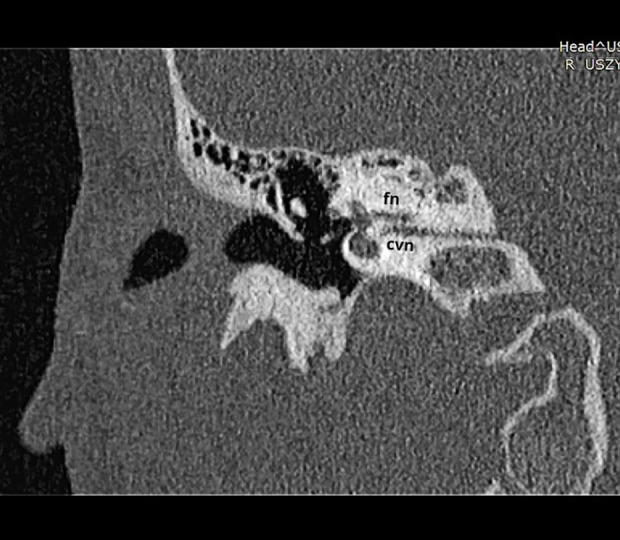

BACKGROUND Duplicated internal auditory canal (dIAC) is a rare congenital temporal bone anomaly associated with ipsilateral sensorineural hearing loss (SNHL). The Bonebridge bone conduction implant has a magnet, an internal transducer, and an external audio processor. This report is of a 14-year-old girl with unilateral SNHL and vestibulocochlear nerve (VIII cranial nerve) aplasia due to dIAC who was treated with a Bonebridge bone conduction implant. CASE REPORT A 14-year-old girl was diagnosed with unilateral hearing loss during a school health check. Her hearing screening at birth was normal. Pure-tone audiometry revealed unilateral deafness in the right ear. CT scan showed a separate canal for the facial and vestibulocochlear nerves. MRI suggested unilateral aplasia of the right nerve VIII. The patient was implanted with a Bonebridge 602 implant in the right ear as a CROS (contralateral routing of signal). During implant activation in the Matrix test with the Bonebridge implant (in SSD configuration), the patient achieved SRT=-10.3 dB SNR. The results of the APHAB questionnaire indicated improvements in hearing. CONCLUSIONS Duplication of the internal auditory canal is pathognomonic for severe cochlear nerve hypoplasia or aplasia. It is important to perform an imaging study before deciding on implantation, as a hearing screening test at birth may not detect congenital hearing loss (embryogenesis of the inner ear and the internal auditory canal occurs independently). In the case of a unilateral anomaly with no hearing impairment on the opposite side, bone conduction implantation should be considered as a CROS.